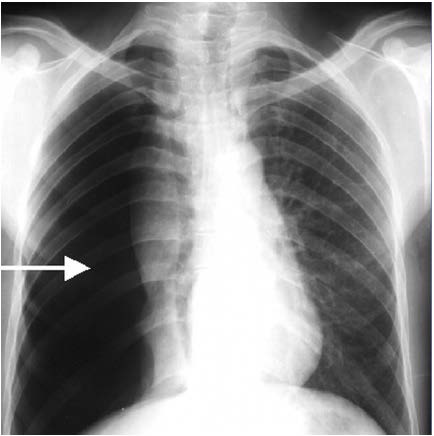

Die chronisch obstruktive Lungenerkrankung (COPD) ist wie oben bereits ausgeführt eine häufige, aber verhinderbare und fortschreitende chronische Atemwegserkrankung, die durch eine chronische Entzündung charakterisiert ist. Diese wird zu 90 Prozent durch Rauchen verursacht und infolgedessen kommt es zur nicht-reversiblen Atemwegsobstruktion mit den Symptomen Husten, Luftnot und Hypoxie. Bei dieser Erkrankung kommt es vor allem beim fortgesetzten Zigarettenrauchen zum Fortschreiten irreparabler Einschränkungen der Lungenstruktur und der Lungenfunktion. Durch diese irreparable Zerstörung der Alveolen kommt es zur Ausbildung eines Lungenemphysems mit Überblähung (unter normobaren Bedingungen, das heißt über Wasser) und dadurch zur Abnahme der Elastizität der Lunge (Abb. 2).

Abb. 2: Computertomographie-Aufnahme des Brustkorbs (CT-Thorax), Transversalebene (axialer Schnitt).

Ausgedehntes Lungenemphysem mit multiplen Emphysembullae (große Blase rechts unten sowie mehrere Blasen links oben und links unten im Bild). Diese Emphysemblasen stellen eine lebensbedrohliche Kontraindikation zur Ausübung des Tauchsports, aber auch für das Schnorcheltauchen dar, da stets die Gefahr der Ruptur und somit die Entstehung eines Pneumothorax (Lungenriss) sowohl in der Kompressions-, als auch in der Dekompressionsphase besteht. © Dr. Dr. Philipp Stahl